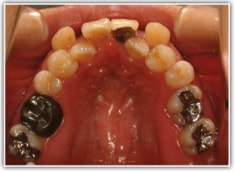

治療後(2年3ヶ月後)

修復歯、補綴歯もあります。下顎8番が水平埋伏しています。

歯根のパラレリング(平行性)が獲得されております。

下顎8番は、両側抜歯済みです。